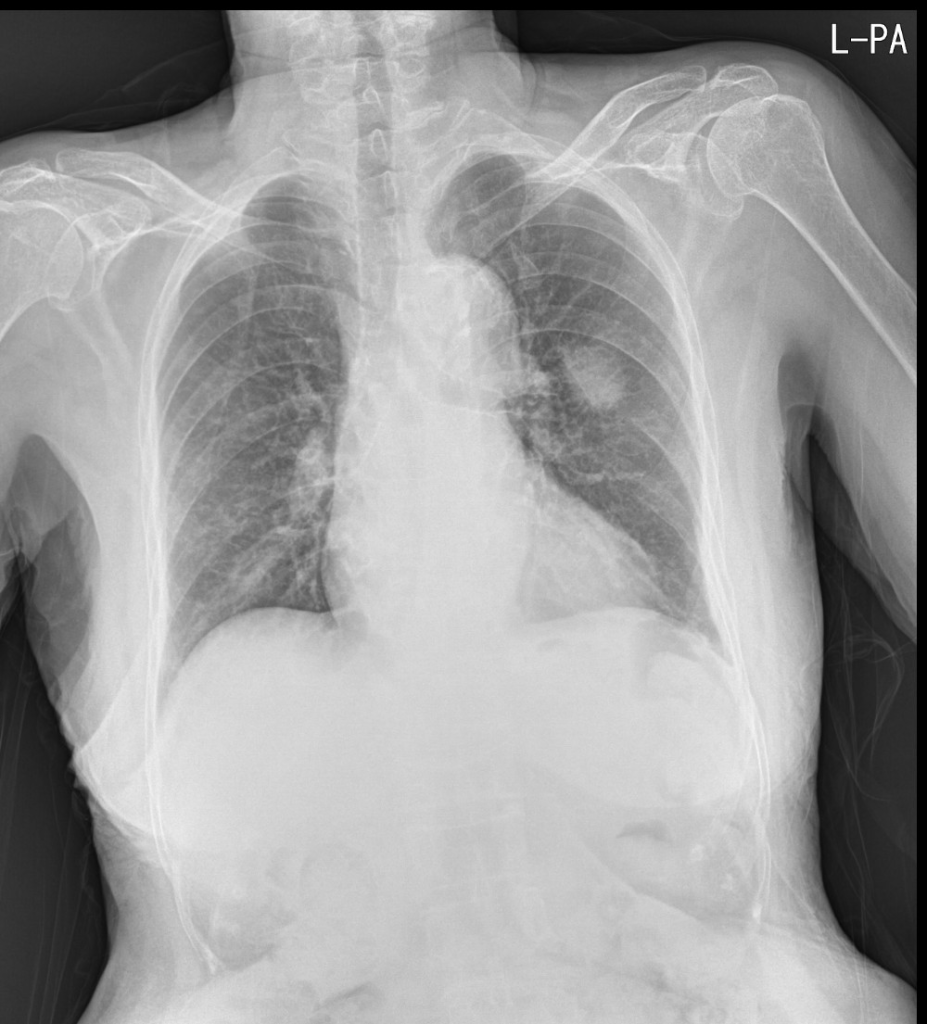

91세 여자 환자로, CT에서 왼쪽 폐에 폐암이 발견되었으나, 고령과 전신상태가 여의치 않아 수술을 포기한 분의 단순 흉부X선 영상입니다.

이전에 여러차례 촬영했던 Chest PA view는 물론 CT에서도 분명히 확인했던 왼쪽 폐의 암덩어리가 AP view에서는 확인되지 않습니다. 이렇게만 보면, 기적적으로 며칠만에 암덩어리가 사라졌든지, 과거 폐암으로 진단되었던 병변이 폐암이 아니라 국소적인 폐렴이었다 며칠만에 호전되었을 가능성도 제기할 수 있을겁니다.

폐에 병변이 의심되는 경우 가장 기초적인 영상검사는 단순흉부X선검사입니다. 특별한 제약사항이 없다면 기본적으로 서있는 자세로 Chest PA view영상을 촬영하는 것이 원칙인데, 왜 AP view가 아닌 PA view를 촬영해야 하는지를 극명하게 보여주는 사례 같아서 올려봅니다.

또한, 의대생이나 영상의학을 전공하지 않은 분이라면 위의 영상들만 보고 Chest PA view인지 AP view인지 정확하게 구별하지 못하는 분들이 있을 수 있지만, 자세히 들여다보면 AP view와 PA view를 구분할 수 있는 중요한 특징들이 잘 드러나있는 영상들입니다. 영상의학과에서 기사분들이 촬영하면서 라벨을 잘못 붙혀서 AP view영상임에도 불구하고 PA view로 잘못 기재되는 경우들이 종종 있고, 이게 나중에 문제가 되는 경우도 있기 때문에 이 둘을 구분하는 건 시험공부로든, 실제 임상영역에서든 상당히 중요한 부분이라 생각합니다.

위의 영상들을 가지고 AP view와 PA view의 구분을 할 수 있는지 잠깐 점검해보는 것도 괜찮을거라 봅니다.